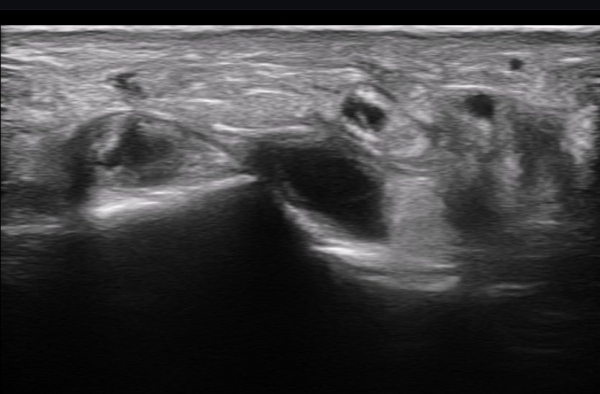

ºñº¹½Å°æ Á¾´Ü¸é°Ë»ç(»çÁø 14, 15)¿¡¼­ ºñº¹½Å°æÀÇ Àü¹ÝÀûÀÎ Àú¿¡ÄÚ ºÎÁ¾°ú ºñº¹½Å°æ ½ÉÃþÀ¸·Î ´Üºñ°ñ°Ç³»

³¶Á¾¼º º¯º¯ÀÌ °üÂûµÈ´Ù.